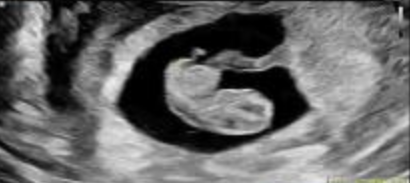

2025年2月,成功进行胚胎移植,一次成功怀孕!

移植之后等待验孕的日子,苏女士以平常心对待,14天后回医院抽血验孕,拿到验孕单的时候,苏女士喜极而泣!